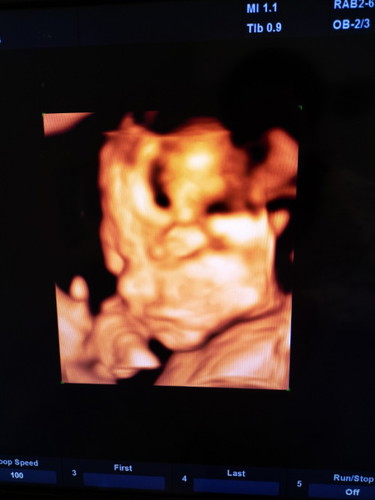

แบบนี้ น้องเป็นปากแหว่งหรือป่าวคะ วันนี้ไปหาหมอมา แล้วขอหมอดูปากน้อง แล้วภาพที่ได้คือภาพนี้ แม่เห็นแล้วใจคอไม่ค่อยดีเลยค่ะ

ตอน 21 วีค เคยให้หมอซาวด์ 4 มิติให้ดูปากแหว่งเพดานโหว่เหมือนกันค่ะ มีเส้นๆตรงกระจับปากเหมือนกัน คุณหมอบอกภาพ 4 มิติ มันเป็นการสร้างภาพขึ้นมา แค่มีอะไรไปบังน้องก็เกิดภาพอย่างนี้ขึ้นได้ค่ะ อยากรู้ว่าเป็นหรือไม่เป็น 2 มิติขาวดำจะดูได้ชัดกว่า แต่ตอนนั้นน้องคว่ำหน้าหนีเลยไม่ได้ดู ล่าสุด 25 วีค เลยขอคุณหมอดูอีกรอบ คุณหมอดูทั้งแบบ 2 มิติขาวดำ และ 4 มิติให้ ลูกปกติดีค่ะ คุณแม่อย่าพึ่งเครียดนะคะ รอคุณหมอคอนเฟิร์มดีกว่าค่ะ

แม่ต้องดูภาพซาว์นขาว/ดำค่ะถ้าซาว์น 4D อาจคลาดเคลื่อนได้ค่ะ หมอจะเช็คน้องปากครบวงไหม วงปากปกติไหมแต่แม่คือน้องหาวให้ดูชัดๆเลยค่ะปกติ แม่ต้องถามหมอค่ะตอนซาว์นปากนี้ปกติไหมแม่ไม่ต้องเครียดค่ะล้านนี้ซาว์น 4D น้องดิ้นก็มีอะไรมาปิดหน้าเหมือนกันค่ะ

หมอซาวด์ให้ แล้วชี้ให้ดูว่าตรงนี้ปากนะ ตรงนี้ตานะ แล้วก็บอกแค่ว่าปกติค่ะ